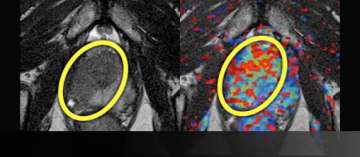

5) Extracapsular Extension and Seminal Vesicle Invasion by MRI + Spectroscopy and Pathology

Extracapsular Extension and Seminal Vesicle Invasion by MRI

• 59 year-old male

• PSA level: 10

• Clinical staging: T1C

• Blind systematic biopsy results: Gleason: 3+4=7 in the Left prostate

• Read More >